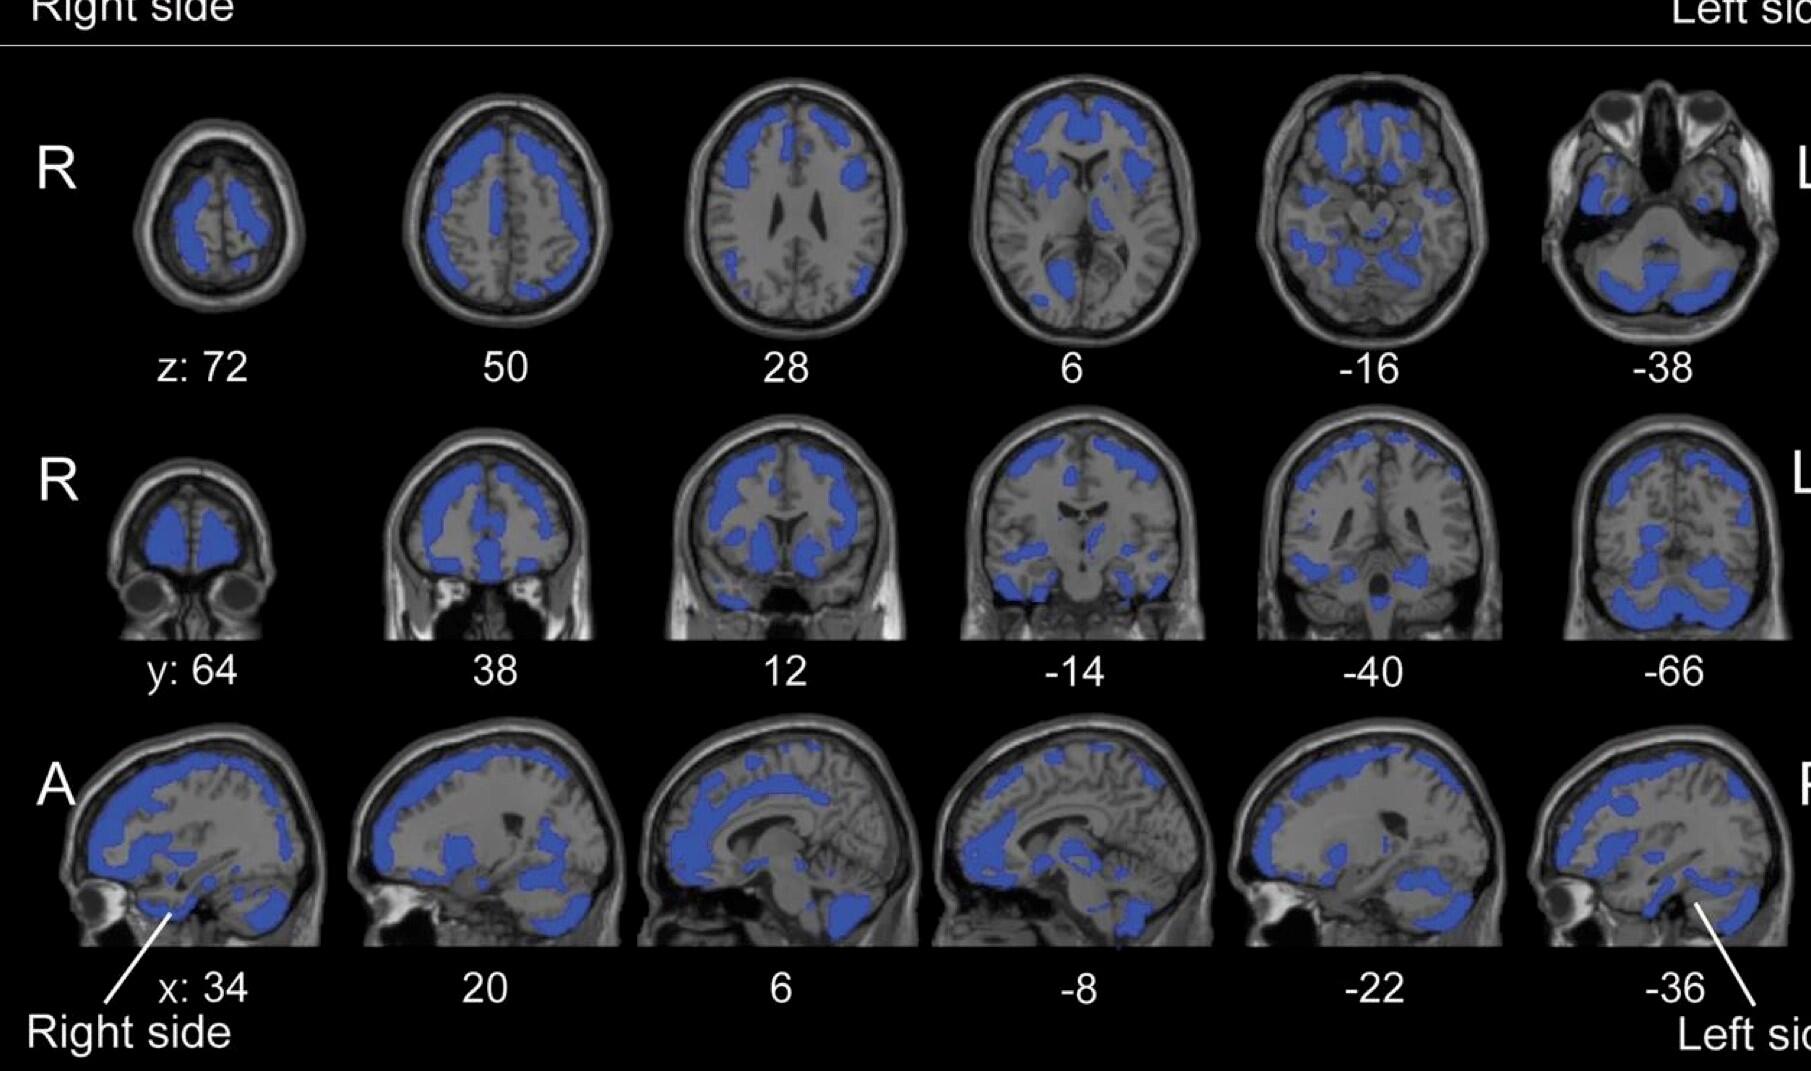

1305夜 『無意識の脳・自己意識の脳』 アントニオ・ダマシオ − 松岡正剛の千夜千冊, 脳を見える化